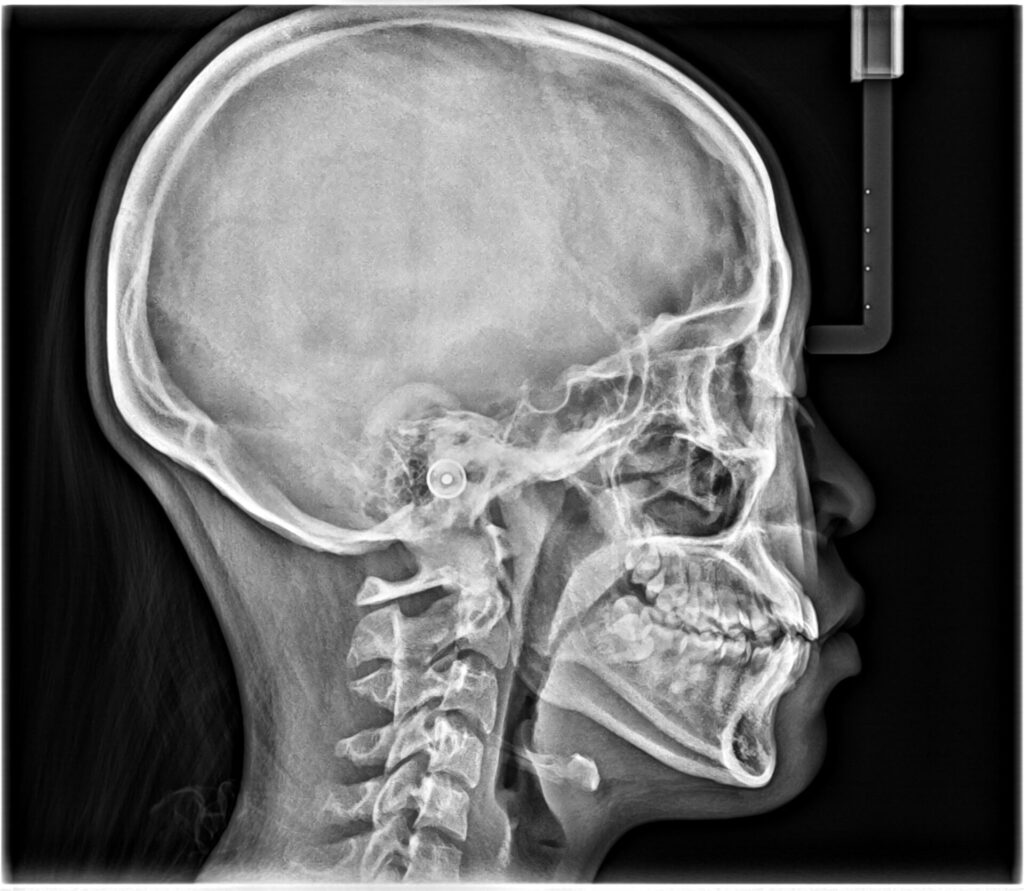

- セファロ(横顔の規格レントゲン)

スキャンによる歯列の確認やレントゲンなどを総合的に検査して矯正のプランニングをする準備をします